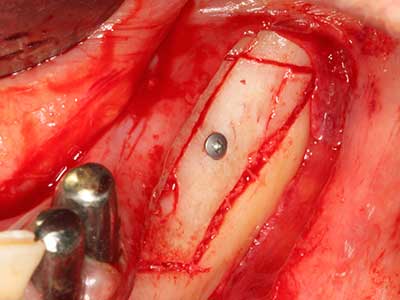

Fig. 21: difetto mascellare esteso dell'incisivo con indicazione per distrazione osteogenetica con tessuto cicatriziale dopo la prima operazione.

Fig. 22: il segmento mobile può essere separato precisamente con la sega sottile per osteotomia (W&H Piezomed).